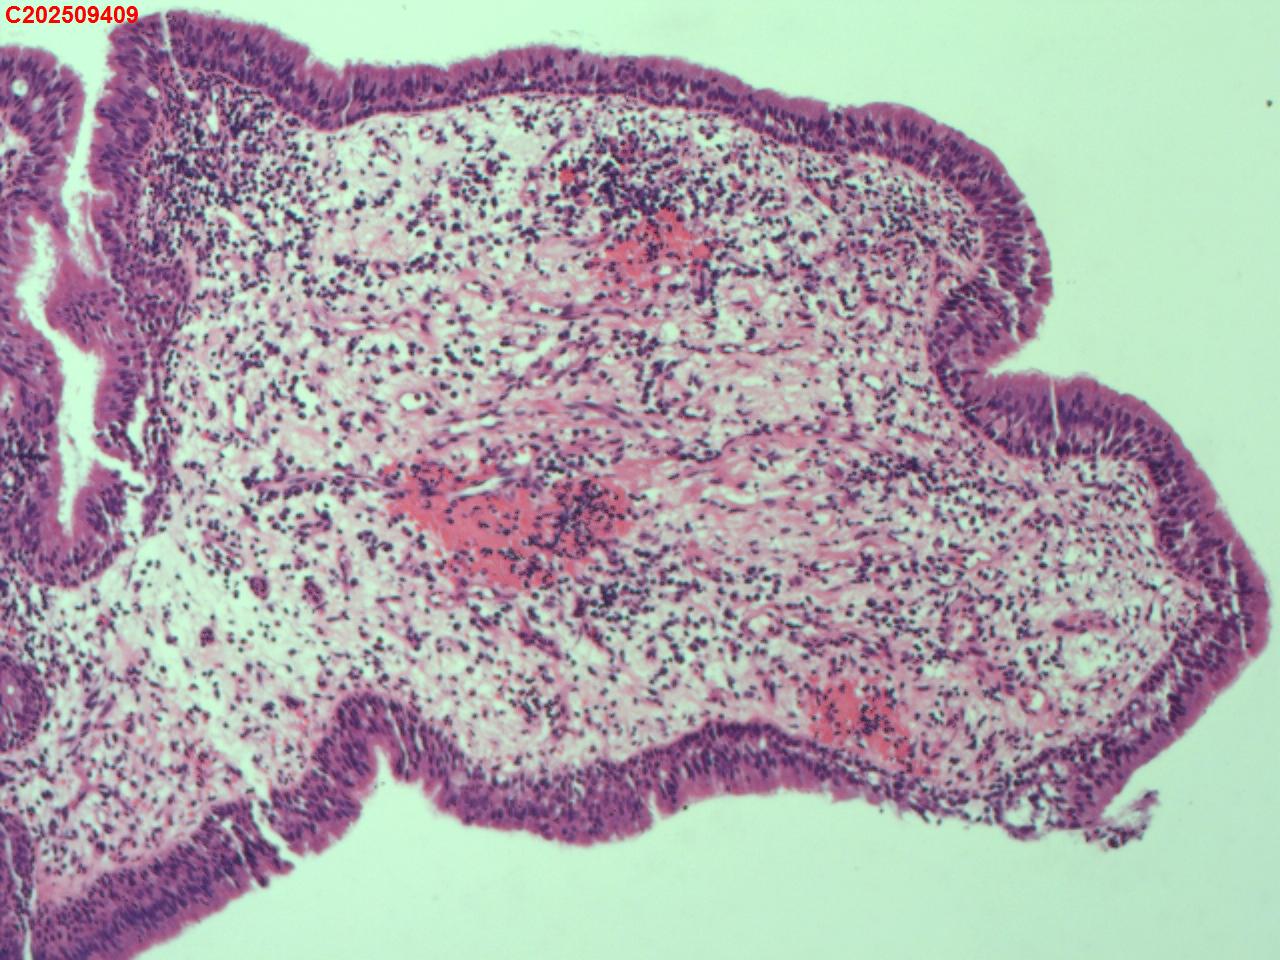

性别年龄62岁临床诊断社区获得性肺炎,肺占位性病变带除外

一般病史胸部CT:双肺可见多发斑片状、结节状高密度影,右肺上叶及左肺下叶病灶内见多发空洞,右侧少量胸腔积液。

标本名称纤支镜咬检

大体所见纤支镜:气管通畅,隆突锐利。右肺主支气管通畅,右肺上叶见少量痰液,负压吸引后见上叶开口干酪坏死物质附着,上叶各段级支气管通畅未见新生物及坏死物质,中叶、下叶背段支气管通畅,下叶基底段见新生物阻塞气道,粘膜无充血。左肺主支气管、上叶、下叶及各段级支气管通畅,粘膜无充血,未见新生物及坏死物。

考虑:支气管炎性息肉